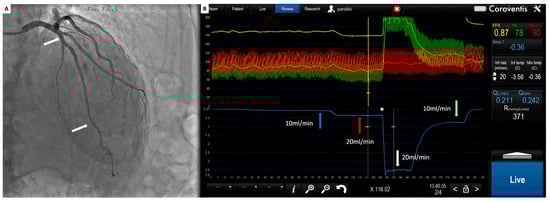

With a 6 Fr guiding catheter positioned in the coronary ostium, a 0.014″ floppy pressure–temperature coronary guidewire is advanced through the coronary artery, after equalization, and located as distal as possible into the target vessel. Thermodilution curves can be obtained with a short manual injection of 3 to 5 mL of saline at room temperature, and a time-based temperature change can be recorded in the distal part of the artery (Figure 4).

Figure 4.

(A) Coronary angiogram. Green arrow: pressure wire sensors; (B) coroventis interface during invasive functional assessment. Red and green pressure tracings represent, respectively, aortic (Pa) and distal coronary pressure (Pd). Blue arrow: intracoronary temperature variation of 3 consecutive boluses of saline at rest. Orange arrow: intracoronary temperature variation of 3 consecutive boluses of saline during maximal hyperemia. Yellow circles: average mean transit time values at rest (Rest) and during hyperemia (Hyp).

Because of the low reproducibility, measurements must be performed three times, taking care not to move the wire during the injections, during two different periods: at baseline and during maximal hyperemia [50].